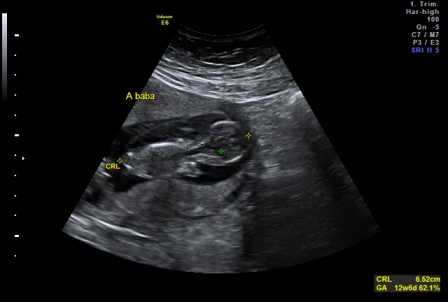

Szandra: Akkor szigorúan tartsd be amit mondanak. Vigyáz a babádra nagyon!!! És a kórházban mit csináltak veled? Infúziót kaptál? Vagy csak megvizsgáltak? ÉS eddig nem látták, hogy lehet hogy két baba van?